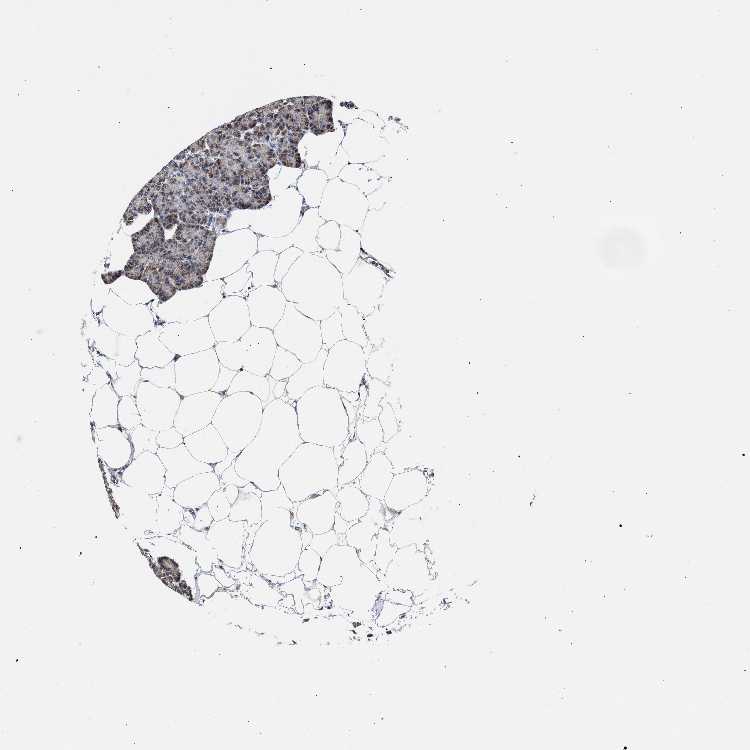

PANCREAS - Antibody stainingi

Antibody staining in the annotated cell types in the current human tissue is reported as not detected, low, medium, or high, based on conventional immunohistochemistry profiling in selected tissues. This score is based on the combination of the staining intensity and fraction of stained cells.

Each image is clickable and will lead to virtual microscopy that enables deeper exploration of all samples and also displays staining intensity scores, fraction scores and subcellular localization as well as patient and tissue information for each sample.

Antibody HPA020081Antibody HPA020103Antibody HPA029476Antibody CAB068194

Exocrine glandular cells HighMediumLowHigh

Pancreatic endocrine cells MediumLowNot detectedMedium